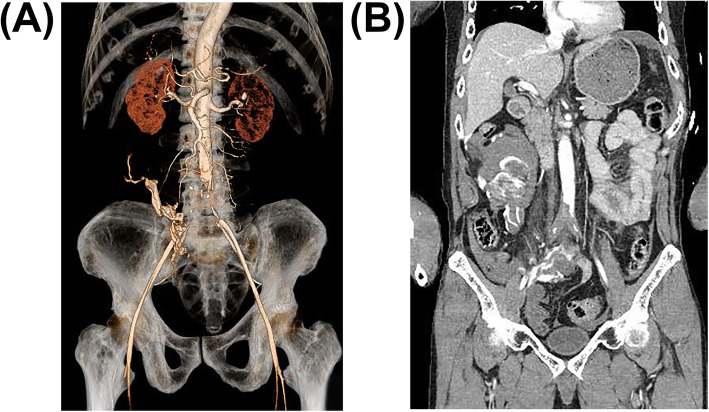

Additional imaging findings were bilateral mandibular fractures, bilateral multiple rib fractures, bilateral pneumothorax, sternal fracture, hematoma around thoracic spine, right clavicle fracture, right ankle debridement injury, and thrombotic occlusion from just above the abdominal aortic bifurcation to the bilateral common iliac arteries (Fig. 1) The intraoperative findings of DCS in the ED revealed no obvious traumatic aortic injury, and a CT scan showed the presence of collateral blood vessels, leading to the diagnosis of Leriche syndrome, which is a chronic arterial occlusive disease. We tried to improve blood flow with intravenous alprostadil (prostaglandin preparation) and continuous intravenous heparin administration.

Fig. 1.

Coronal computed tomographic (CT) reconstructions in arterial phase images. A Complete occlusion just above the bifurcation of the abdominal aorta on 3D-CT image. In particular, the collateral blood pathway to the right external iliac artery can be seen. B Coronal contrast-enhanced CT images show disruption of blood flow due to bilateral thrombi at the aortic bifurcation and distal blood flow